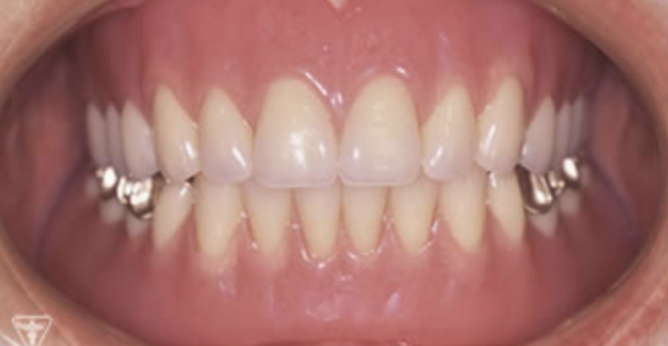

症例

お困りごとを参考に、治療のbefore・afterが確認できます。治療過程や期間、費用などを参考にご覧ください。